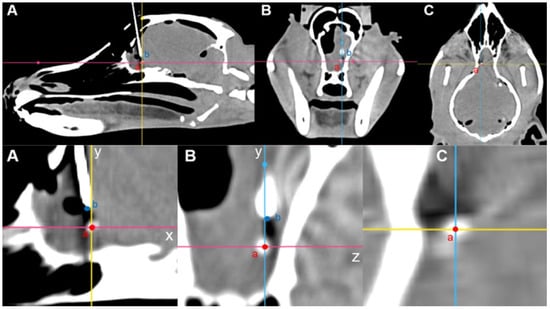

Intraoperative CT images were transmitted to Mimics Medical software (version 21.0; Materialize NV, Leuven, Belgium) for stereolithography (STL) file generation, similar to preoperative imaging. Segmentation was performed using appropriate thresholding techniques to isolate the skull, 3D guides, spinal needle, and tumor model. Subsequently, the STL files were transferred to computer-aided design software (Fusion 360, Autodesk, San Rafael, CA, USA). Using Fusion 360 software (Autodesk, San Francisco, CA, USA), preoperative and intraoperative STL files were fused to assess the needle placement errors. The preoperative skull was aligned with the intraoperative skull, and the endpoints of the spinal needle tip, the center point of the target ROI, and the center point of the tumor model were marked. The distance between the needle tip point and center point of the target ROI was measured. The relative orientation of the spinal needle tip point was determined using the sagittal, dorsal, and transverse views. The distance between the needle tip point and the center point of the tumor model was measured, and the positional relationships were assessed (Figure 8).

Figure 8. Calculation of needle placement error in the fronto-olfactory lobe after inserting a spinal needle, as assessed by the 3D volume-rendering method. (A) The center of the tumor model was designated as point ‘a’, the end of the spinal needle as point ‘b’, and the center of the ROI was designated as point ‘c’. (B) The spatial relationships of the three points in the transverse view. (C) The spatial relationships of the three points in the axial view. The distance between each point can be measured using the measurement function.